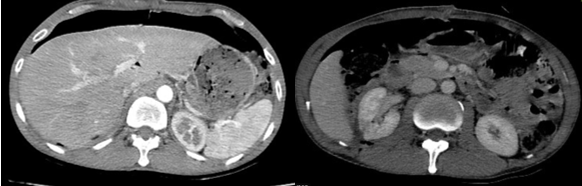

Hình ảnh chụp chụp cắt lớp vi tính ổ bụng sau phẫu thuật 1 tuần (03/2025): Hình ảnh sau mổ u sau phúc mạc bên phải, hiện thấy tụ dịch-khí khoang sau phúc mạc kèm ống dẫn lưu bên trong. Khí tự do ổ bụng (sau mổ). Khí trong mạc treo ruột. Dịch tự do ổ bụng

Hình 3. Hình ảnh chụp cắt lớp vi tính ổ bụng: Hình ảnh sau mổ u sau phúc mạc bên phải, hiện thấy tụ dịch-khí khoang sau phúc mạc  (sau mổ 1 tuần)

- Hình ảnh chụp cắt lớp vi tính ổ bụng (4/2025): Hình ảnh sau mổ u sau phúc mạc bên phải, hiện thấy tụ ít dịch mỏng, đám thâm nhiễm khoang sau phúc mạc. Ít dịch ổ bụng vùng hạ vị.

Hình 4. Hình ảnh chụp cắt lớp vi tính ổ bụng: sau mổ u sau phúc mạc bên phải, hiện thấy tụ ít dịch mỏng, đám thâm nhiễm khoang sau phúc mạc (sau mổ 1 tháng)